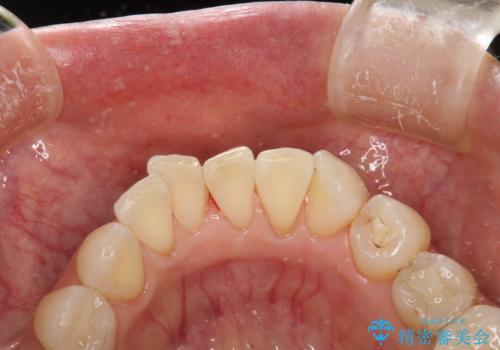

PMTCで歯と歯の間の細かいステインの除去

- 歯磨きでは取れない歯と歯の間の汚れが気になるとのことで来院されました。PMTC60分コースを行いました。

毎日丁寧に歯磨きをしていても、日常生活での飲食物などにより着色してしまうことはあります。PMTCでは、歯の表面の凸凹にミネラルを補給して、ツルツルの表面に仕上げます

歯科医院にて、適切な処置を行うことで、長期的に安定したお口の環境が作られます。まずはカウンセリングなどもおススメです。